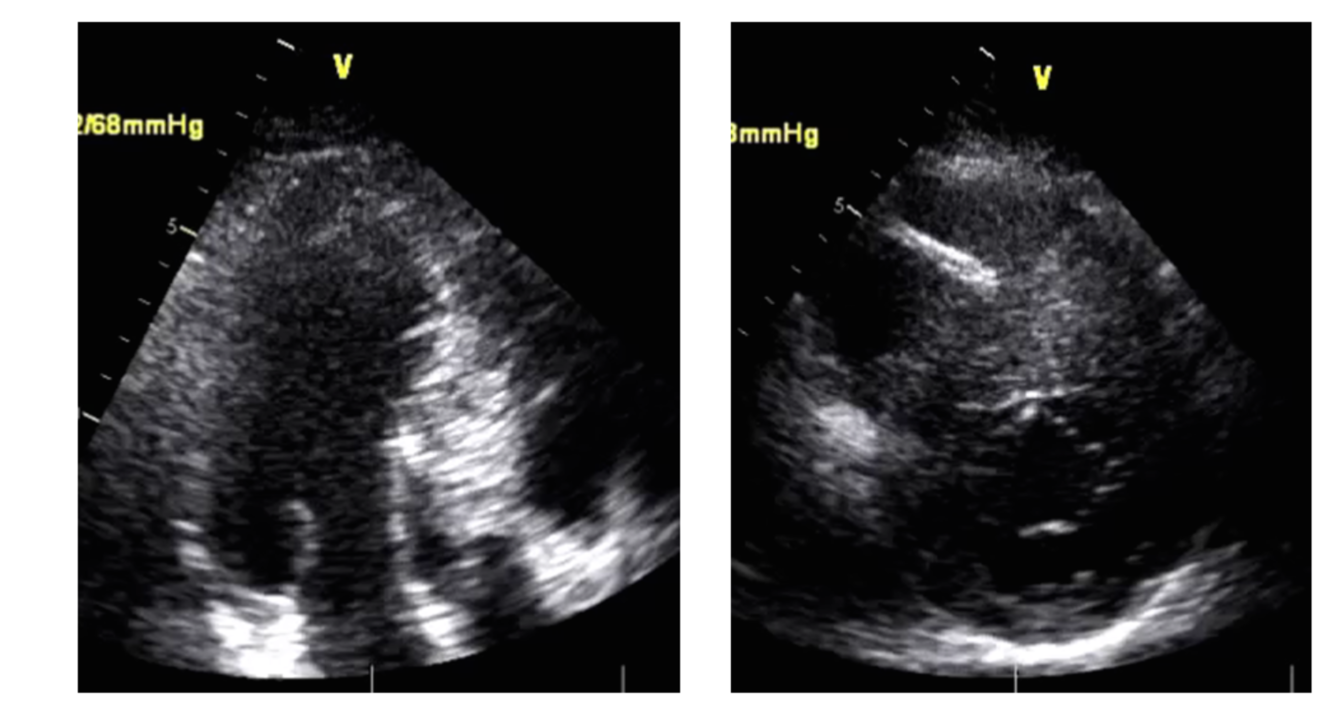

small chamber size and thick walls = HCM or Athelte?

HCM (athlete’s have higher EDD > 55mm )

LVEDD< 45mm = athlete vs HCM?

HCM (Athlete LVEDD> 55)